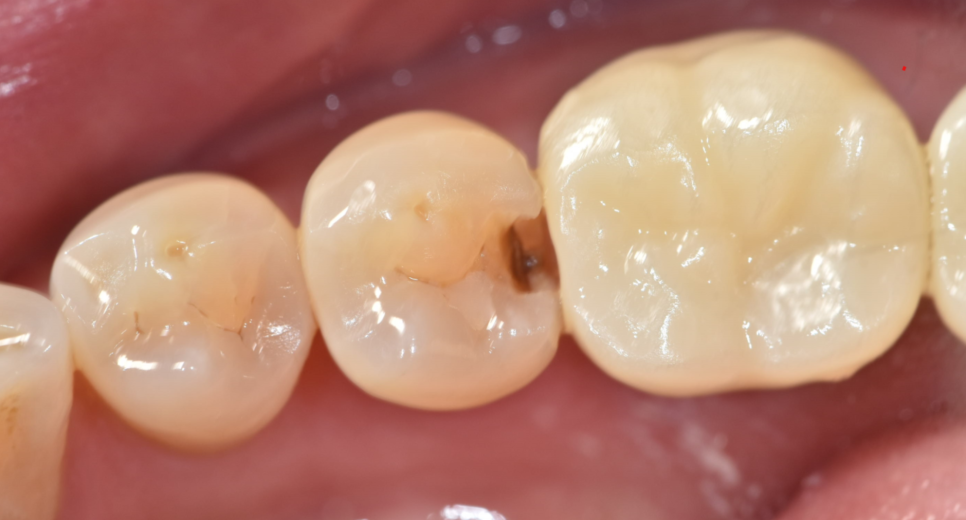

치아가 깨졌을 때 단계적 치료방법

어금니 치아 파절

범위에 따라 치료가 결정됩니다.

치아가 살짝 깨진 정도라면 레진이나

인레이 같은 간단한 치료로 원래 형태를 복원할 수 있습니다.